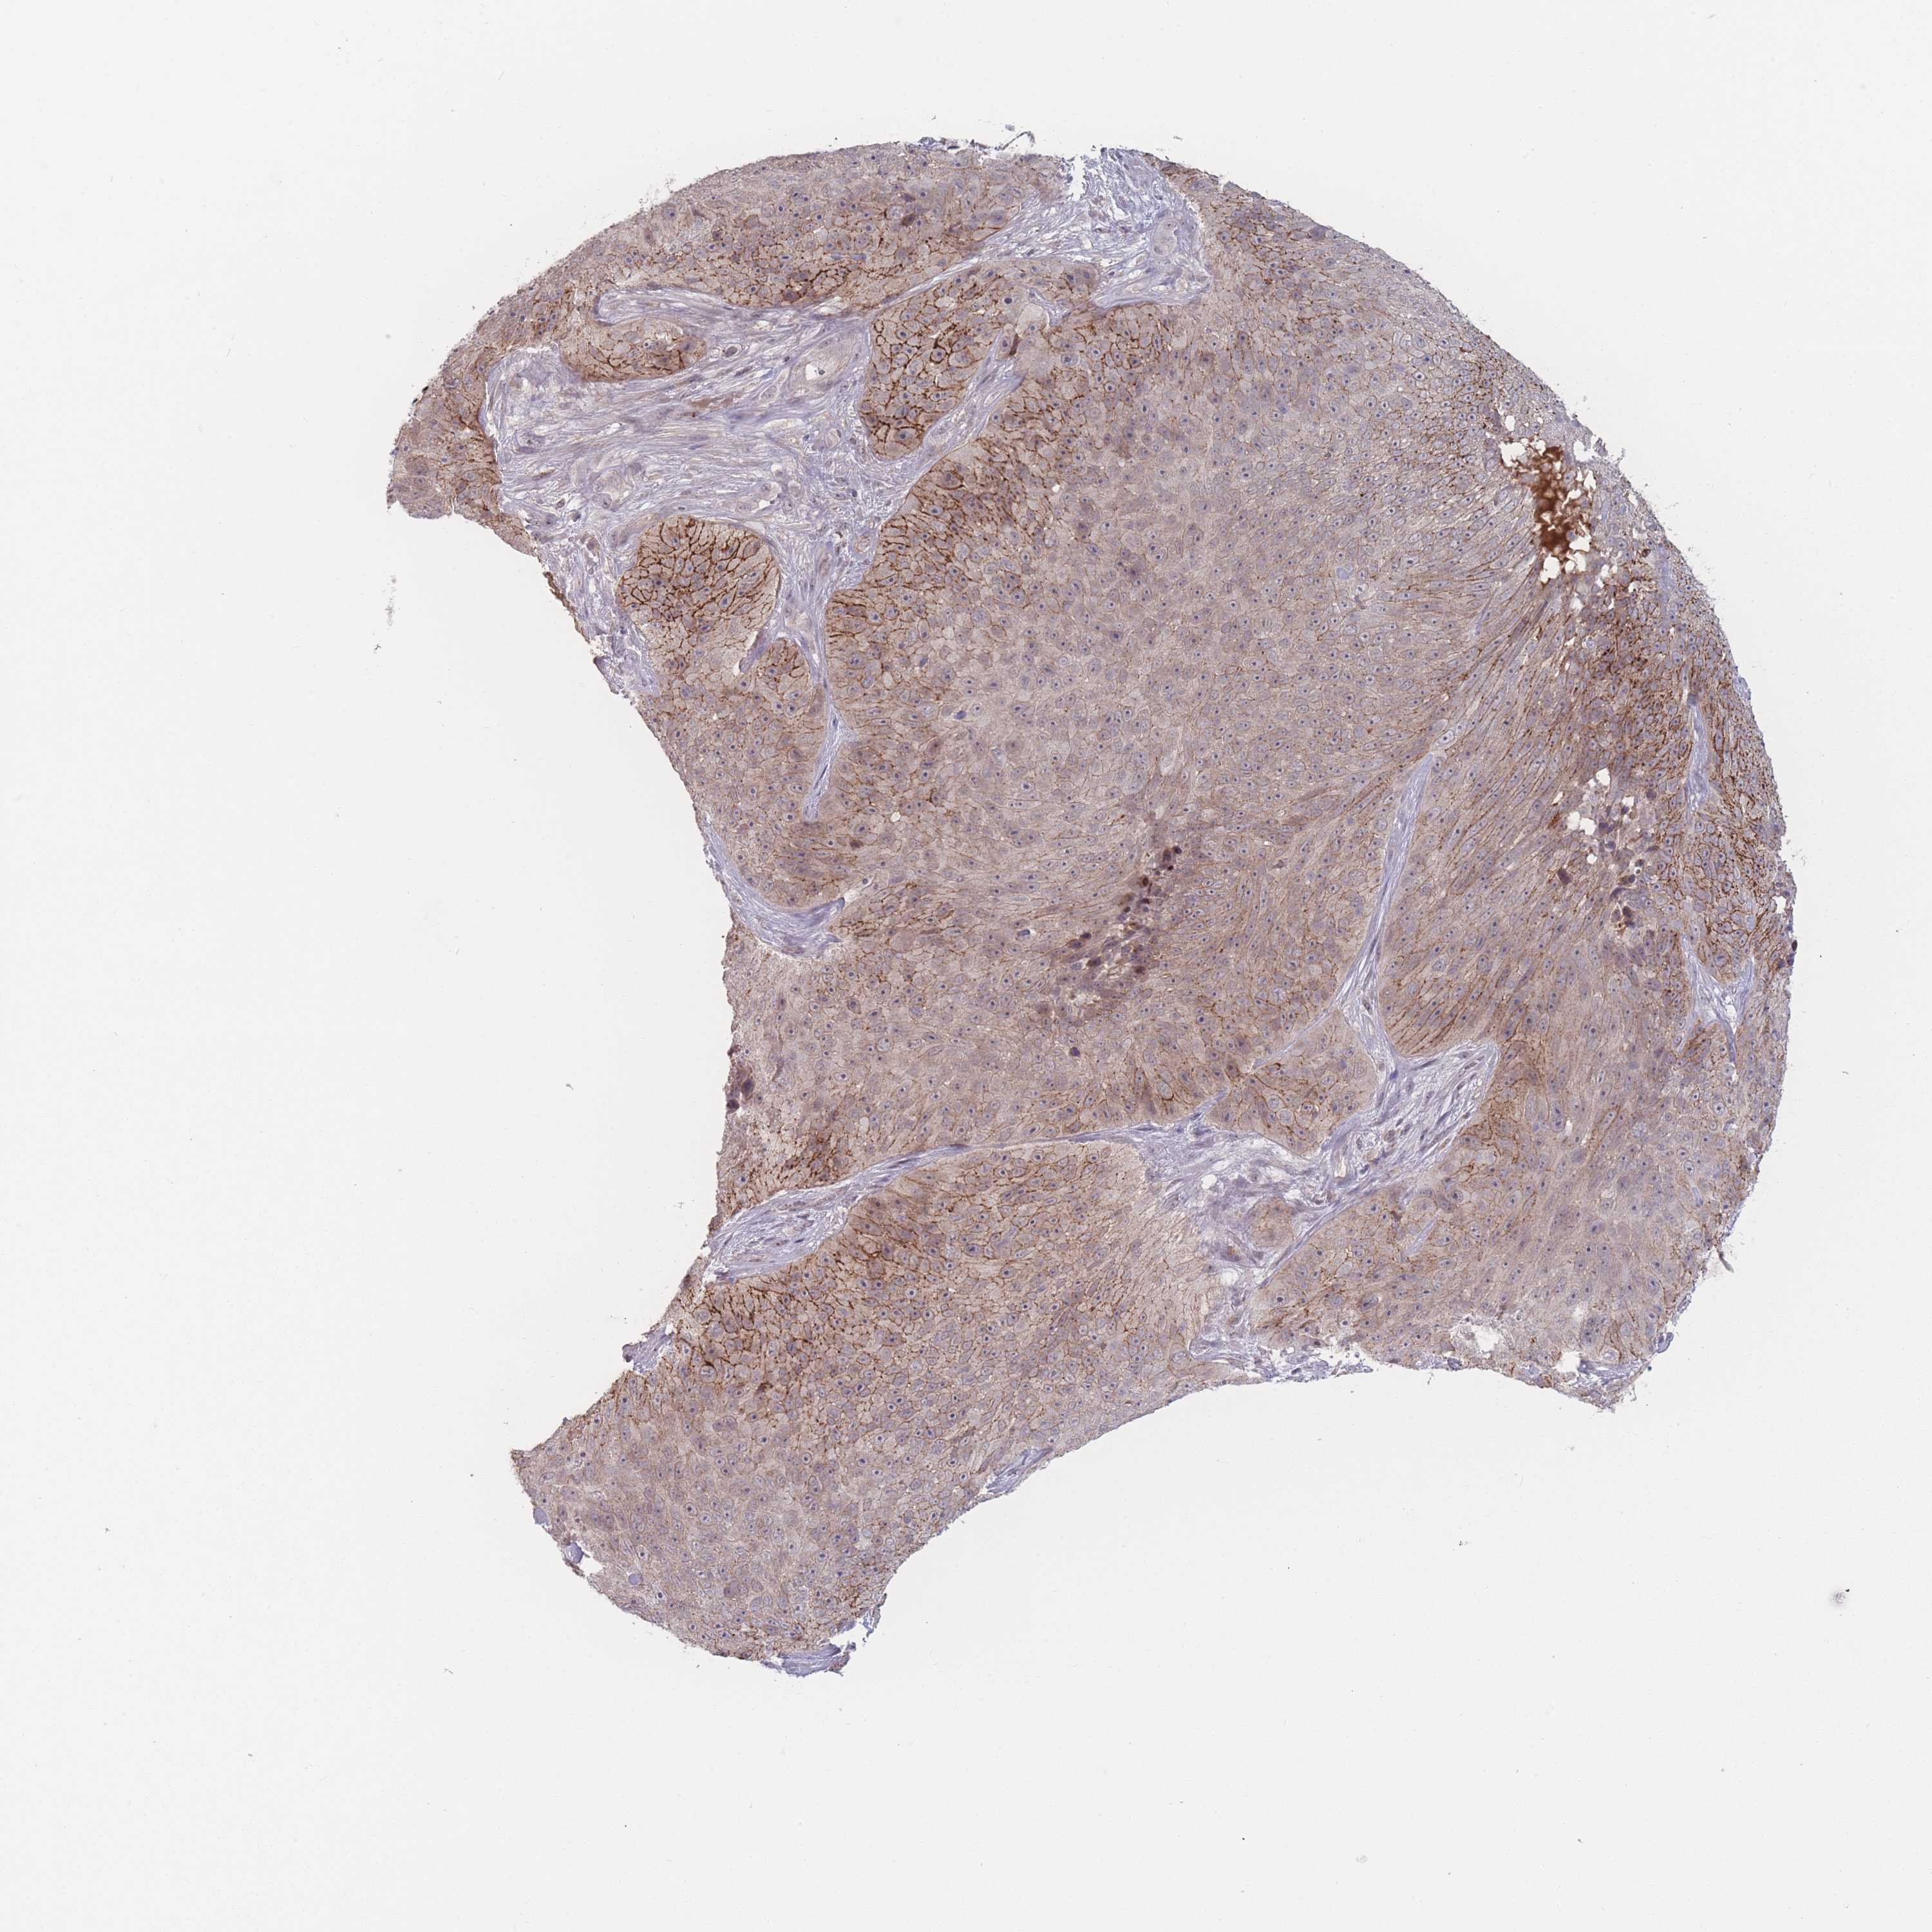

SKIN CANCER - Protein expressioni

A mouse-over function shows sample information and annotation data. Click on an image to view it in a full screen mode. Samples can be filtered based on level of antibody staining by selecting one or several of the following categories: high, medium, low and not detected. The assay and annotation is described here.

Antibody staining in the annotated cell types in the current human tissue is reported as not detected, low, medium, or high, based on conventional immunohistochemistry profiling in selected tissues. This score is based on the combination of the staining intensity and fraction of stained cells.

Each image is clickable and will lead to virtual microscopy that enables deeper exploration of all samples and also displays staining intensity scores, fraction scores and subcellular localization as well as patient and tissue information for each sample.

Antibody HPA049386

Staining

High

Medium

Low

Not detected

Intensity

Strong

Moderate

Weak

Negative

Quantity

>75%

75%-25%

<25%

None

Location

Nuclear

Cytoplasmic/membranous

Cytoplasmic/membranous,nuclear

Basal cell carcinoma

Squamous cell carcinoma, NOS

Squamous cell carcinoma, metastatic, NOS